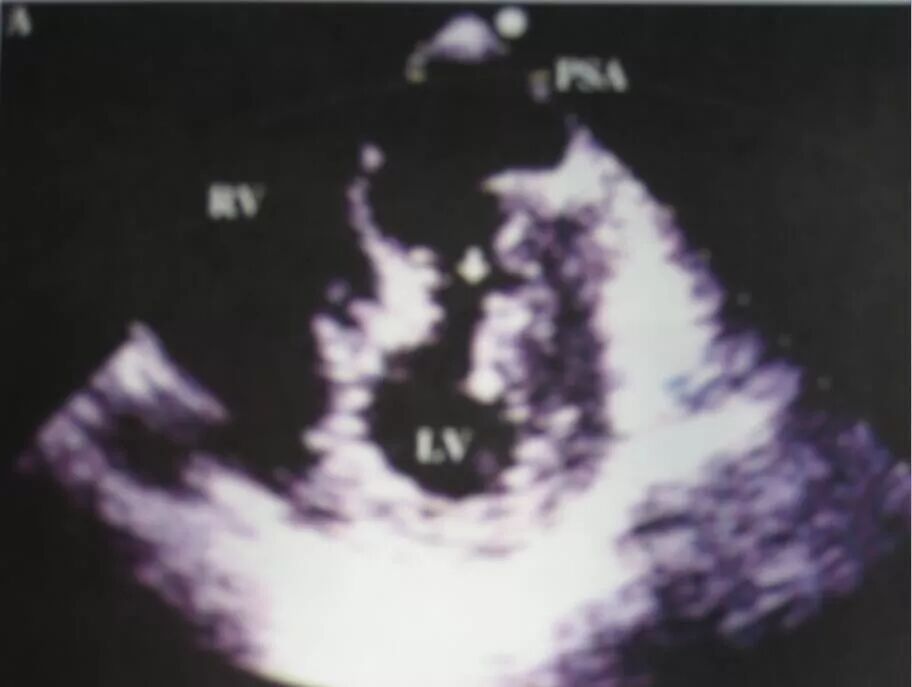

1.真性室壁瘤:通常发生于心肌梗死后5天到3个月内,甚至在一年内发生。发生率占心梗患者的3.5%--38%。病变常累及心肌各层,好发于左室前壁、心尖部和室间隔下2/3处。

真性室壁瘤超声表现为心腔局限性外凸,收缩期瘤壁扩张,舒张期缩小;瘤壁心肌变薄,与正常心肌间有连续性 ,病变基底部较宽;瘤壁呈矛盾运动或运动消失;彩色血流显示瘤体内血流束暗淡,血流方向不定。